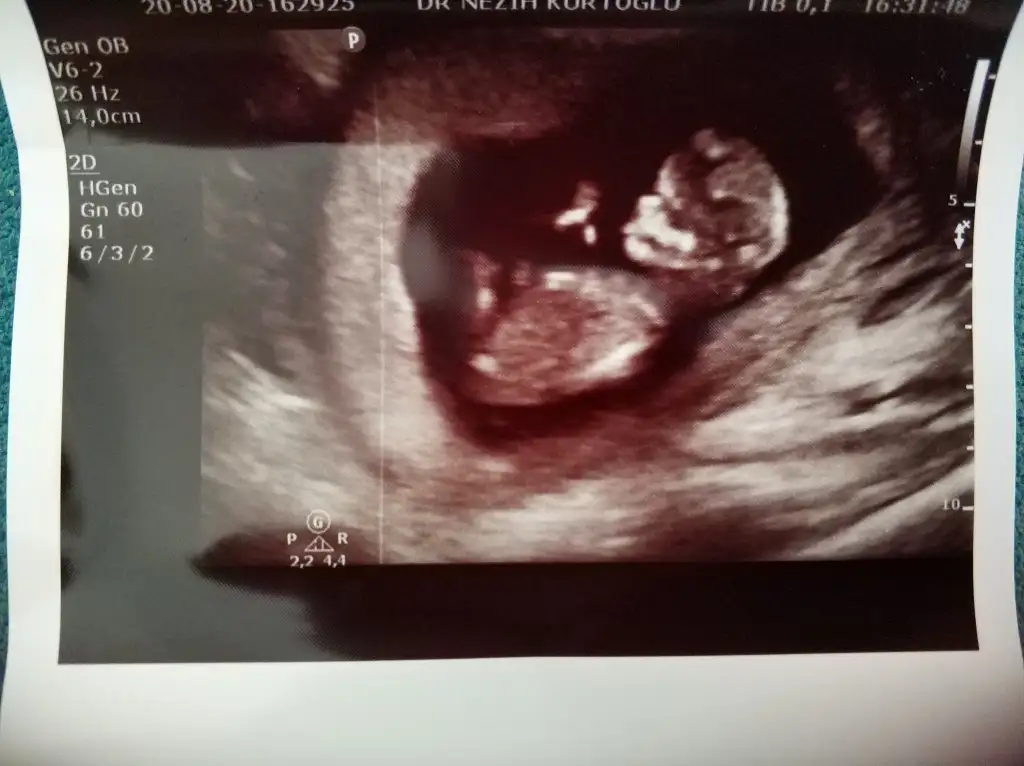

Google den girdim oldu harbiden teşekkürler : ) bakın bakalım benim bebeğimin cinsiyetine bir de bütün fotoğraflarda aynı mı yani kızsa hepsinde kız mı görünüyor erkekse hepsinde erkek mi görünüyor onu söyleyin ben neden hepsinde farklı gördüm acaba.. Ayrıca USG görüntüleri 11 ve 12. Haftalar arasına ait..Yeni üyeyim fotoğraf nasıl yükleniyor acaba yaa bulup da gönderemiyorum yardımcı olur musunuz?? Dosya ekle seçeneğini seçiyorum hiçbir ekran gelmiyor..

Hepsi kız görünüyorGoogle den girdim oldu harbiden teşekkürler : ) bakın bakalım benim bebeğimin cinsiyetine bir de bütün fotoğraflarda aynı mı yani kızsa hepsinde kız mı görünüyor erkekse hepsinde erkek mi görünüyor onu söyleyin ben neden hepsinde farklı gördüm acaba.. Ayrıca USG görüntüleri 11 ve 12. Haftalar arasına ait..

Yaaa gerçekten miiiiii... Ama doktor bana erkek dedi hatta pipisini bile gösterdi.. Bende hep kızım olsun istiyorum acaba kız mı ki yaaa... Şuan 14 haftalığım doktor tam 12 haftalıkken dedi erkek diye...Hepsi kız görünüyor

Ben kız istediğim için doktora emin misiniz belki değişecek ne belli dedim doktor bana güldü evet yanılma payı olabilir 15 16. Haftalar arası en net denilir ama ben sana yine erkek diyeceğim dedi yaaa.. Ama çok acayip istedim ki kızım olsun.. O yüzden belki sizden kız çıkar diye sormak istedim. Teşekkür ederim bakalım ne çıkacakKıza gibi nubu12 hafta cok erken 15-16 olsa doğrudur diyecemde tabi Dr daha detaylı bakar birdaki randevuda netleşir